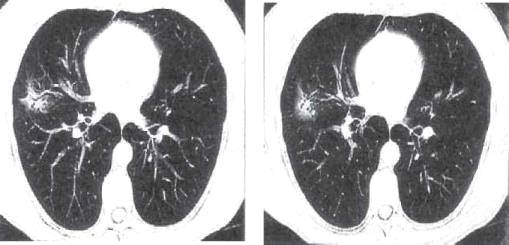

Рис. 11.5. Бронхолобулярный инфильтрат во II

сегменте правого легкого. КТ.